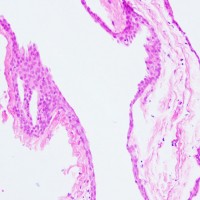

前頭側頭開頭 pterional approachで全摘出しました。発生母地は下垂体柄前面でしたが完全摘出しました。術後に下垂体機能は正常に保たれています。病理所見は一層の上皮細胞でのう胞壁が構成されることが特徴です。これをラトケのう胞と呼ぶかどうか議論のあるところで,おそらく正確には内胚葉のう胞 endodermal cystと診断します。